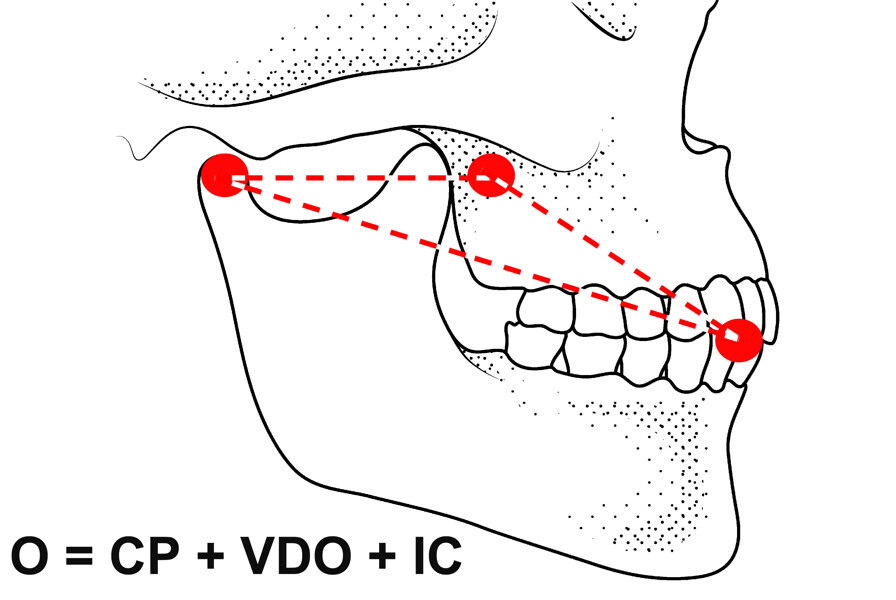

Fig. 5: Occlusion represented as mandibular position and intercuspation.